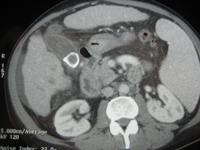

Diverticulose colique